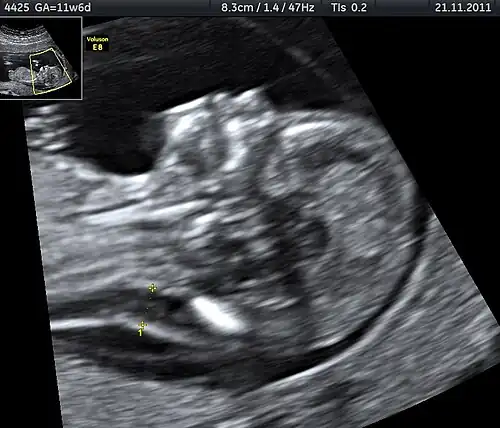

| Ultrasound is often used to diagnose stillbirth and medical conditions that raise the risk. | |

| Diagnostic method | No fetal movement felt, ultrasound[5] |

Often the cause is unknown.[1][12] Causes may include pregnancy complications such as pre-eclampsia and birth complications, problems with the placenta or umbilical cord, birth defects, infections such as malaria and syphilis, and poor health in the mother.[2]: Causes tab, [3][13] Risk factors include a mother's age over 35, smoking, drug use, use of assisted reproductive technology, and first pregnancy.[4] Stillbirth may be suspected when no fetal movement is felt.[5] Confirmation is by ultrasound.[5]

It is unknown how much time is needed for a fetus to die. Fetal behavior is consistent and a change in the fetus' movements or sleep-wake cycles can indicate fetal distress.[30] A decrease or cessation in sensations of fetal activity may be an indication of fetal distress or death,[31][32] Still, medical examination, including a nonstress test, is recommended in the event of any type of any change in the strength or frequency of fetal movement, especially a complete cease; most midwives and obstetricians recommend the use of a kick chart to assist in detecting any changes.[33] Fetal distress or death can be confirmed or ruled out via fetoscopy/doptone, ultrasound, and/or electronic fetal monitoring.[34] If the fetus is alive but inactive, extra attention will be given to the placenta and umbilical cord during ultrasound examination to ensure that there is no compromise of oxygen and nutrient delivery.[35]